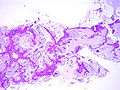

Additional images

Mucinous BAC

Non-mucinous BAC